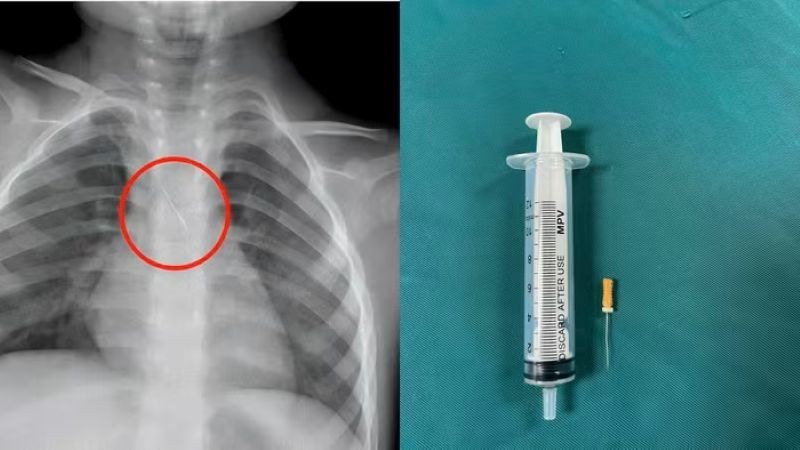

Dị vật trong đường thở của bệnh nhi. (Ảnh: Bệnh viện Đa khoa tỉnh Quảng Trị)

Trước đó, bệnh viện tiếp nhận bệnh nhi N.Q.T.Đ, 3 tuổi, trú tại xã Cửa Việt, Quảng Trị trong tình trạng ho nhiều, ho sặc. Kết quả chụp phim cho thấy 1 dị vật kim loại dài khoảng 22mm nằm ở góc carina (vị trí chia đôi khí quản) đe dọa gây tắc nghẽn đường thở.

Ngay lập tức, các bác sĩ hội chẩn liên khoa và quyết định nội soi phế quản cấp cứu. Dị vật được phát hiện có một đầu nhọn cắm vào 1/3 dưới khí quản, đầu còn lại nằm trong phế quản gốc trái.

Sau 15 phút thao tác khẩn trương, dị vật được kíp mổ lấy ra an toàn. Bé trai cải thiện triệu chứng ngay sau can thiệp và xuất viện sau 48 giờ theo dõi.